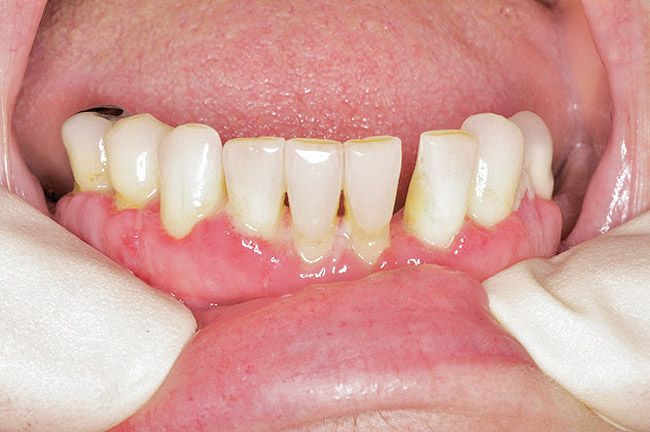

Under the sextant approach, one quadrant is treated and the patient is left to heal for 2 months before proceeding to any additional quadrants. While the patient heals, a 10-day course of antibiotics and 2 months of twice-daily chlorhexidine rinsing may be prescribed. Figure 4 shows a patient who was taking oral bisphosphonates for 3 years and was treated with the sextant approach. As seen in the radiograph, the patient has one molar in the lower right quadrant. This tooth was extracted and the patient was given 2 months to heal (Figure 5 and Figure 6). The patient was placed on antibiotics and chlorhexidine rinse. After 2 months, no signs of BRONJ were observed, and the anterior teeth were scheduled for extraction. They were extracted as atraumatically as possible, and the site was sutured (Figure 7 and Figure 8).The patient then was given another 2 months to heal, following the previous protocol. After 2 months of healing, no BRONJ was observed (Figure 9).

Figure 5  After 2 months of healing, the lower right quadrant showed no signs of BRONJ and the anterior teeth were scheduled for extraction.

Figure 5

Figure 6  After 2 months of healing, the lower right quadrant showed no signs of BRONJ and the anterior teeth were scheduled for extraction.

Figure 6

Figure 7  Anterior extraction sites after atraumatic removal.

Figure 7

Figure 8  Sutures were placed after extraction.

Figure 8

Figure 9  For this quadrant, no signs of BRONJ were observed after 2 months of healing.

Figure 9